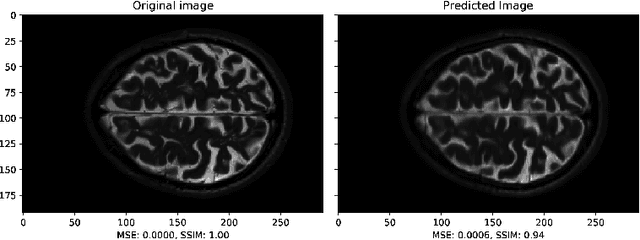

Abstract:Multiple sclerosis is one of the most common chronic neurological diseases affecting the central nervous system. Lesions produced by the MS can be observed through two modalities of magnetic resonance (MR), known as T2W and FLAIR sequences, both providing useful information for formulating a diagnosis. However, long acquisition time makes the acquired MR image vulnerable to motion artifacts. This leads to the need of accelerating the execution of the MR analysis. In this paper, we present a deep learning method that is able to reconstruct subsampled MR images obtained by reducing the k-space data, while maintaining a high image quality that can be used to observe brain lesions. The proposed method exploits the multimodal approach of neural networks and it also focuses on the data acquisition and processing stages to reduce execution time of the MR analysis. Results prove the effectiveness of the proposed method in reconstructing subsampled MR images while saving execution time.